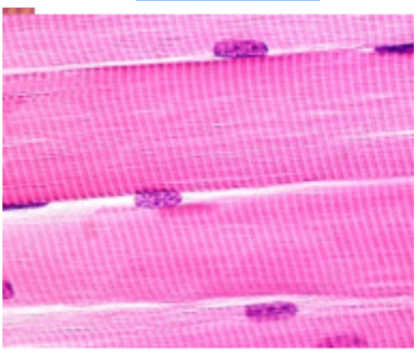

What is this?

Muscle tissue